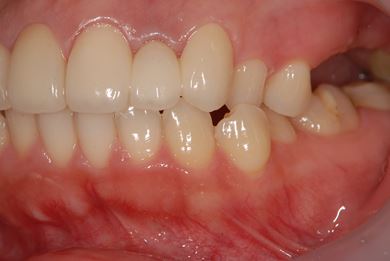

セラミック治療+骨造成(欠損部)

| 性別/年齢 | 女性 / 34歳 | ||||||||||||||||||||||||||||||||

| 治療方針 | 上顎前歯1歯抜歯し、オールセラミックブリッジ、クラウン、ラミネートベニアにて審美的回復を行う。 | ||||||||||||||||||||||||||||||||

| 治療内容 | オールセラミッククラウン2本、ジルコニアフレームオールセラミックブリッジ3本、オールセラミックラミネートベニア2本、骨造成(欠損部) | ||||||||||||||||||||||||||||||||